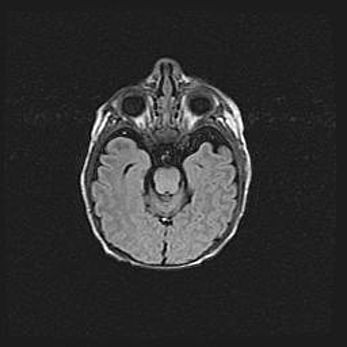

Множественные кисты обоих полушарий головного мозга, наибольшая из них в правой затылочной области. Ассиметричная атрофическая гидроцефалия.

Возраст: 7 месяцев

Вес: 5660 г

Пол: мужской

Окружность головы: 41,5 см

Срок гестации: 28-29 недель

Кисты головного мозга развиваются в результате многоочаговых некрозов вещества мозга и возникают вследствие перенесенной перинатальной инфекции, менингитов, энцефалитов, асфиксии, родовой травмы, расстройств мозгового кровообращения различного генеза. Образованию кист в веществе головного мозга плодов и новорожденных способствуют такие факторы, как высокое содержание в нем воды, недостаточная (или отсутствие) миелинизация и слабая астроглиальная реакция на повреждение.

Кисты могут сочетаться с гидроцефалией и другими поражениями головного мозга.